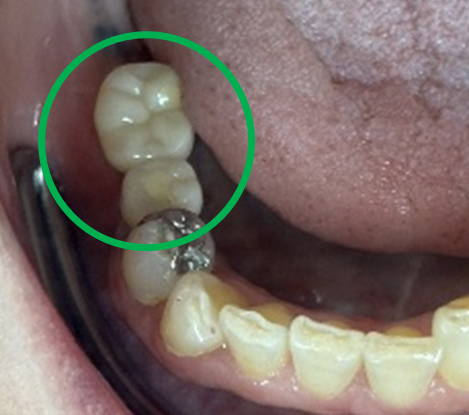

After

※緑丸は、今回埋入したインプラント

※黄色丸は、2006年10月に埋入したインプラント